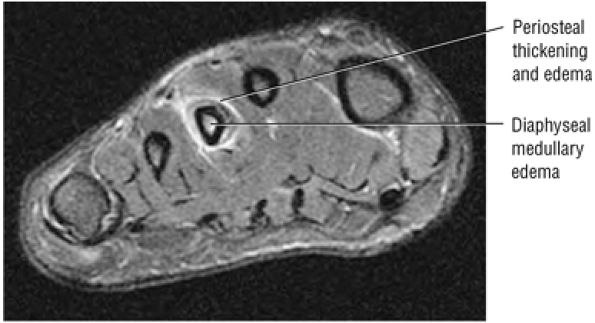

![]() |

|

FIGURE 5.58 ● transverse section through the midcalf shows the anterior and lateral compartments and their contents.